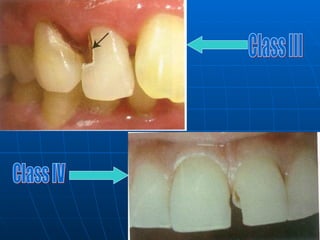

Class 3 lesions: Lesions found on the proximal surfaces of anterior teeth that do not involve or necessitate the removal of the incisal angle. Class 4 lesions: Lesions found on the proximal surfaces of anterior teeth that involve the incisal angle. Class 5 lesions : Lesions that are found at the gingival third of the facial and lingual surfaces of anterior and posterior teeth. Class 6 (Simon’s modification ): Lesions involving cuspal tips and incisal edges of teeth .

Class III Class IV

Class 3 lesions:Lesions found on the proximal surfaces of anterior teeth that do not involve or necessitate the removal of the incisal angle. Class 4 lesions: Lesions found on the proximal surfaces of anterior teeth that involve the incisal angle. Class 5 lesions : Lesions that are found at the gingival third of the facial and lingual surfaces of anterior and posterior teeth. Class 6 (Simon’s modification ): Lesions involving cuspal tips and incisal edges of teeth .